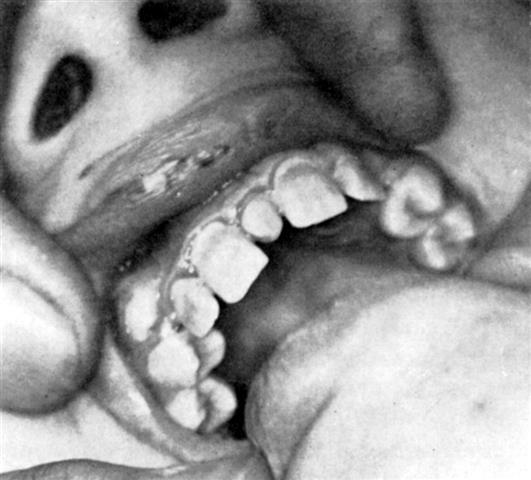

A gauche = dents d'HUTCHINSON (influence de la syphilis) sur la croissance et la minéralisation imparfaite).

Noter la présence d'une dent surnuméraire ("mesiodens") entre les incisives centrales.

A droite = polycaries évoquant Kreosotum

D’abord, comme le dit si bien M. CONAN-MERIADEC, il y a le problème de l’enfant que les aléas de la vie intra-utérine d’abord, puis dès son autonomie après sa naissance ont soumis aux facteurs étiologiques du mode luétique et qui voit sa croissance plus ou moins perturbée,  en particulier mais non exclusivement ses dents et ses maxillaires, dont les remèdes de fond préventifs ou curatifs sont CALCAREA FLUORICA et FLUORIC ACID. ou SILICEA. On trouve chez cet enfant des stigmates semblables aussi bien  à ceux que provoque une intoxication chronique par le fluor qu’à ceux que suscite la syphilis elle-même. Et il est bien intéressant de comparer les conséquences dentaires de la syphilis (les dents d’HUTCHINSON) et celles de la fluorose. C’est ce que nous montrerons plus loin.